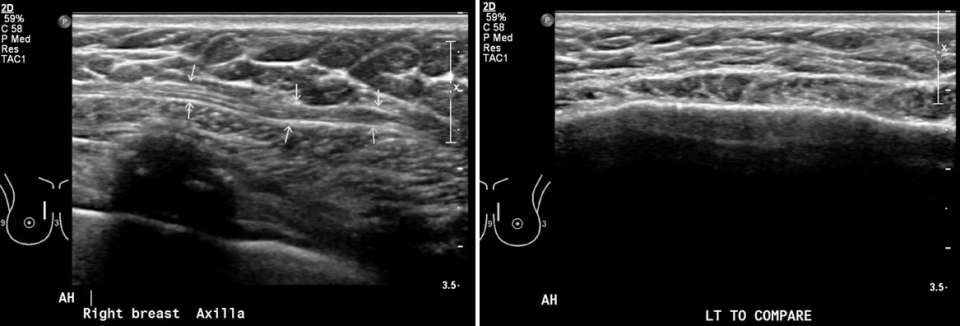

Case: Sternalis Muscle Figure 5

Right breast: Fibrillar structure superficial to the underlying pectoral, consistent with sternalis muscle. Left breast: Obtained for comparison, no accessory muscular structure is seen.